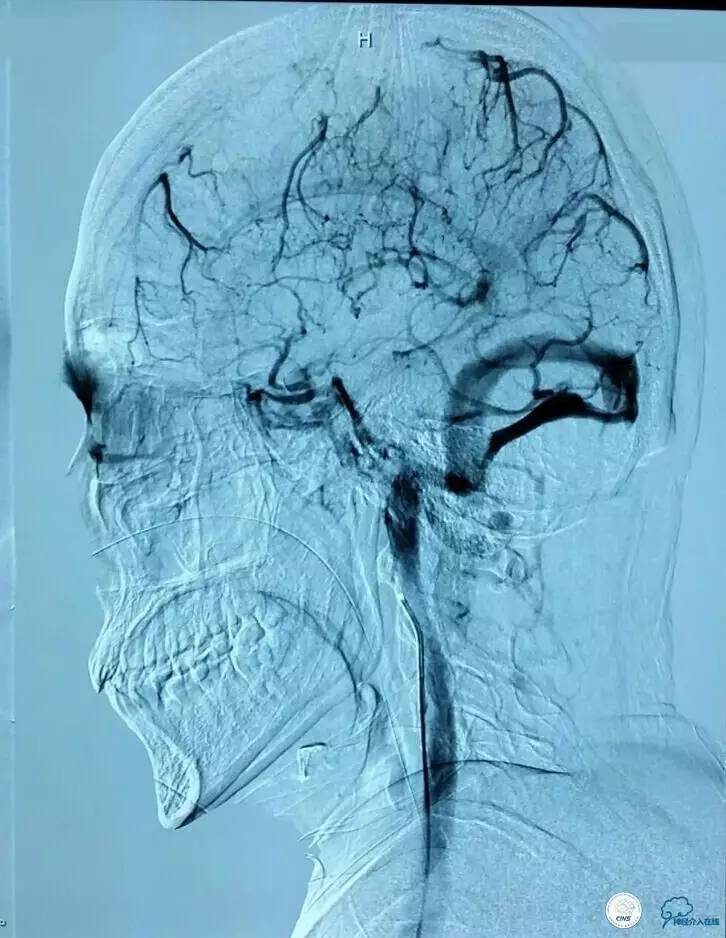

▼术前造影和MRV一致: